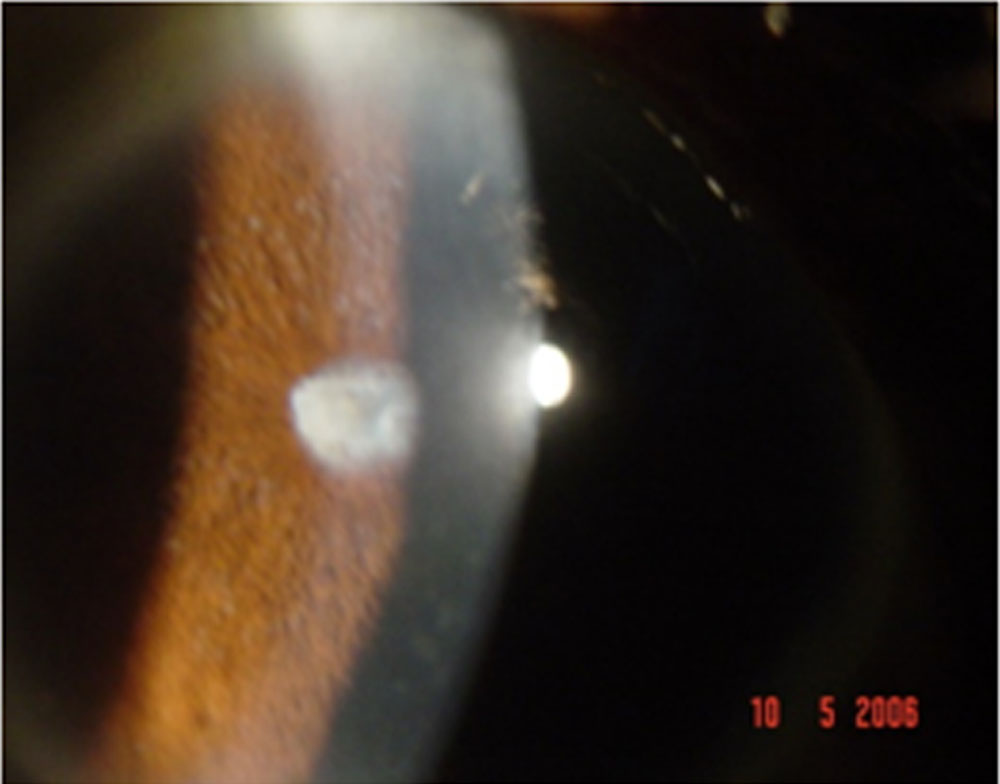

38% showed acute anterior uveitis and 62% showed chronic anterior uveitis. It was granulomatous in 83% with the predominant clinical feature being iris sphincter atrophy and dilated pupil with large mutton keratic precipitatesand anterior chamber cells and flare. 17 % of patients presented with a non- granulomatous iridocyclitis although that is not a usual presentation in uveitis. Cataract was noted in 33% of patients. On morphological evaluation, posterior subcapsular cataract was the most common feature and both senile and complicated cataract were seen. Several of our patients had dilated pupil due to iris sphincter atrophy. Vitritis was present in 3% of patients and was seen as grade 2 cells with vitreous haze. Fundus examination was normal in all patients. 12% of patients had scleritis of the nodular type. Those with scleritis showed resolution with topical steroids with no recurrence and a scraping was not performed on them. Treatment for iridocyclitis was 1% atropine eye drops,1% prednisolone acetate eye drops and oral steroids in the dose of 1mg per kg bodyweight In those with no resolution to this treatment for more than 3 weeks, an anterior chamber paracentesis was performed. RT- PCR performed on the aqueous humour of 12 patients with recalcitrant uveitis showed detection of DNA of M. leprae in 3 of them. A smear in these patients showed the presence of live and dead bacilli. Microscopy showed the typical morphology of fully formed live bacillus and beaded dead bacilli both existing in the same sample. After completion of treatment, the onset of uveitis in the paucibacillary type occurred within 1 year in 9% of patients, 2 years in 33% and within 3 years in 11%. Those with multibacillary leprosy had recurrence of uveitis after 3 years of completion of treatment. No patients had uveitis before that time period.

- Figure 1: Mutton fat keratic precipitates and iris pearls

Figure 1: Mutton fat keratic precipitates and iris pearls